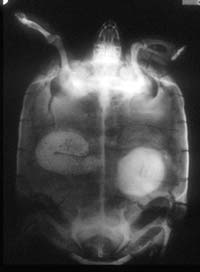

![]() This desert tortoise has a large bladder stone in the left lobe of the bladder (visible on the right side of the photo). The stone is pinching off the intestine, causing constipation. |

A stone the size of the one that you describe in your tortoise is very large and has probably been there for a long time. I think all stones should be removed, as they will not go away and will only get bigger.